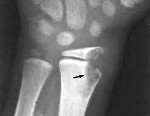

• Туберкулез лучезапястных суставов. При такой редкой форме заболевания поражаются кости и сустав запястья.

Чтобы выявить костный туберкулез, специалист направляет больного на рентгенограмму. С ее помощью определяют первые признаки заболевания – остеопороз. Возникает такая патология при вымывании кальция из костей и разрушении перегородок в костной ткани. Рентгенограмма выявляет образования в полости сустава, размытые контуры пораженной кости, неровную хрящевую поверхность, сужение суставной щели. Если имеется абсцесс, то проявляется он в виде тени около очага поражения.

Когда заболевание находится в активной стадии, то на снимках врач выявляет отсутствие суставных щелей, разрастание патологического очага, образование полостей с вкраплениями или белковым содержимым, разрушение трабекул. При прогрессировании туберкулез суставов поражает соседнюю костную ткань. В фазе затухания рентгенограмма обнаруживает восстановленные трабекулы, уменьшение остеопороза и атрофических явлений, четкие контуры кости.

• Лучезапястный сустав. Еще одна редкая форма заболевания. Наблюдается поражение сустава и костей запястья, обычно двухстороннее. Часто сочетается с туберкулезом локтевого или коленного сустава.